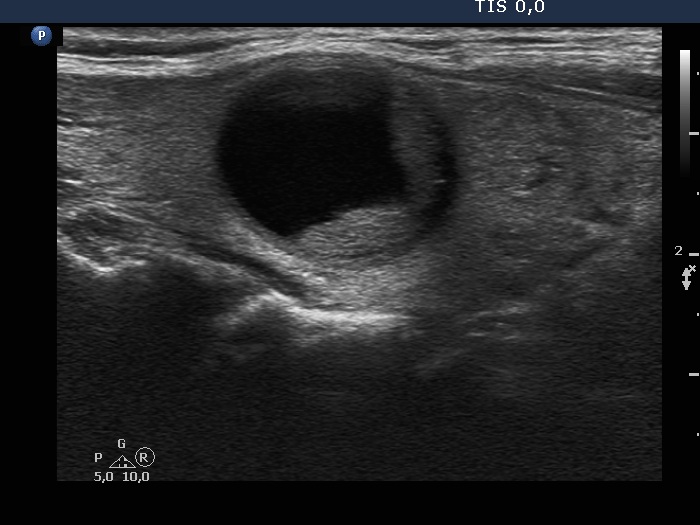

Ultrasonography. The thyroid was echonormal and had multiple moderately hypoechoic and hyperechoic nodules which showed various degrees of cystic degeneration. The largest nodule in the right lobe was dominantly cystic and presented with minimally hypoechoic solid part which included hyperechoic figures. The largest nodule in the left lobe had irregular margins.

2.5 mL cystic fluid was aspirated from the right nodule. Thereafter, the borders became irregular, lobulated. Aspiration cytology of the solid part after the removal of cystic fluid an that of the nodule having irregular borders in the left lobe resulted in bening cystic degeneration.

The nodule' borders became irregular after aspiration of cystic fluid. This is a phenomenon which should not be regarded as a pathological finding.